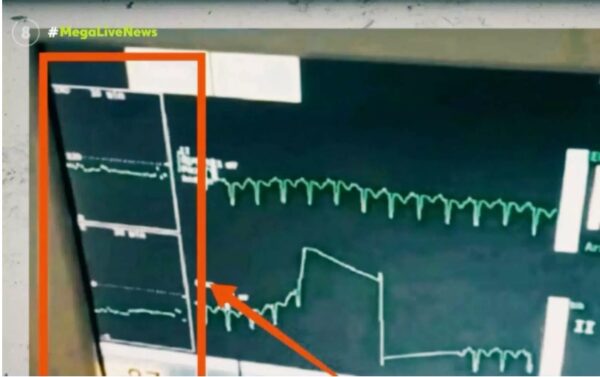

Πάτρα: Η μυστηριώδης βραδυκαρδία της Τζωρτζίνας – Νέο ντοκουμέντο για την καρδιακή της λειτουργία

Νέες αποκαλύψεις έρχονται στο φως σχετικά με τον θάνατο των τριών παιδιών στην Πάτρα, καθώς υπάρχει νέο ντοκουμέντο για την καρδιακή της λειτουργία της Τζωρτζίνας και την κρίσιμη ένδειξη στο μόνιτορ με τους παλμούς του παιδιού.